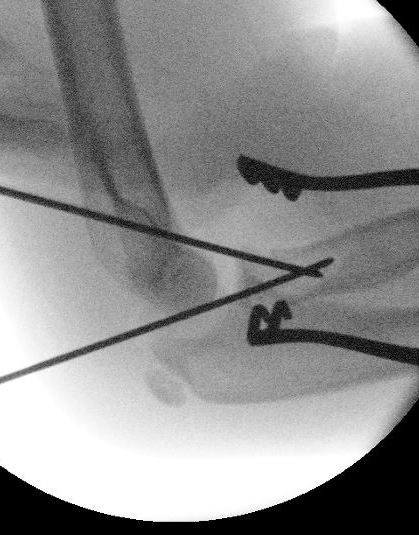

Retrograde flexible nail

Technique

Entry point through radial styloid

- closed reduction +/- percutaneous K wire reduction

- engage tip into radial neck

- Metaizeau technique - rotate nail to reduce radial fracture